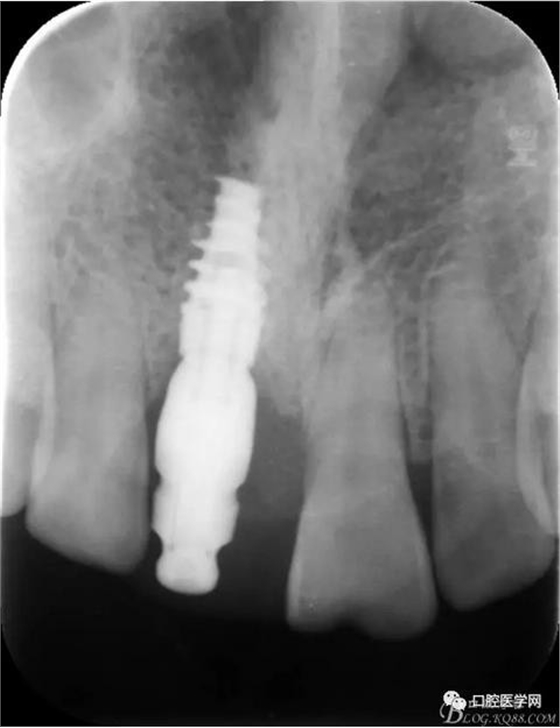

X 光 示:11 根折,根尖無(wú)明顯異常

診 斷:11 根折

圖1 術(shù)前X光片